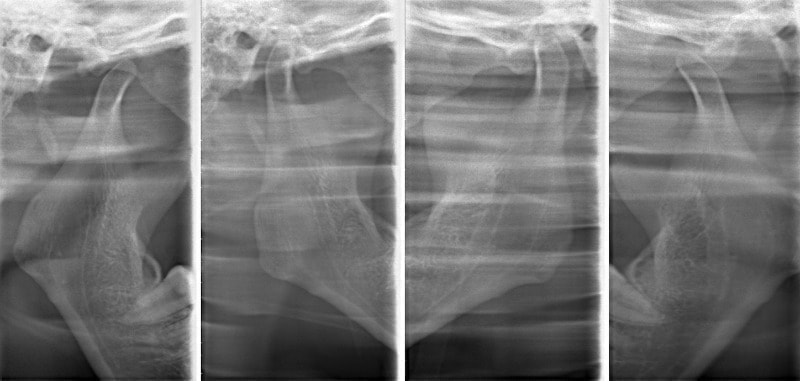

検査時顎関節レントゲン

関節頭に変形が認められます。